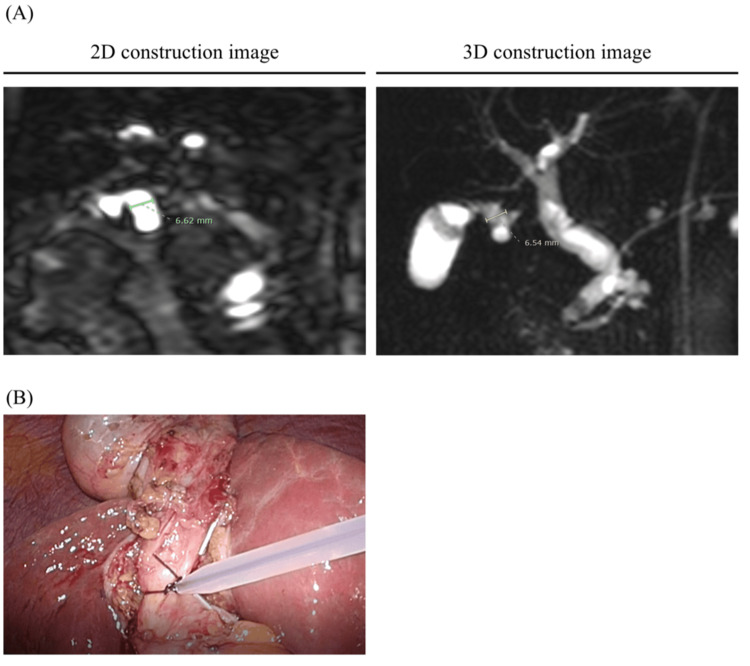

MRCP imaging was performed on patients after an overnight fast using 3.0 T MRI scanners (Achieva 3.0T TX, Philips, Amsterdam, Netherlands). The diameter of the CD and CBD was measured using MRCP imaging and employing 2D or 3D imaging to assess the clarity of the construction. The length of the CD was detected from just below the Hartmann’s pouch, and the CBD was measured after connecting it (Figures 1, 2). The anatomical variation of the CD was defined via 3D construction from MRCP imaging as previously reported [ref. 14]. If the 3D image was unclear, we used the 2D image instead. Different surgeons in our department measured these sizes.